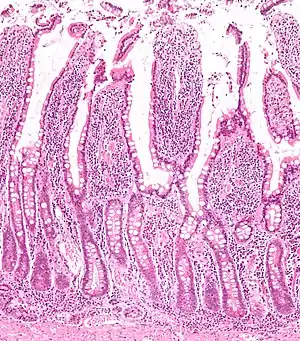

Tracing has revealed that LGR5 is a marker of adult intestinal stem cells. The high turnover rate of the intestinal lining is due to a dedicated population of stem cells found at the base of the intestinal crypt. In the small intestines, these LGR5+ve crypt base columnar cells (CBC cells) have broad basal surfaces and very little cytoplasm and organelles and are located interspersed among the terminally differentiated Paneth cells.[12] These CBC cells generate the plethora of functional cells in the intestinal tissue: Paneth cells, enteroendocrine cells, goblet cells, tuft cells, columnar cells and the M cells over an adult's entire lifetime. Similarly, LGR5 expression in the colon resembles faithfully that of the small intestine.[12]